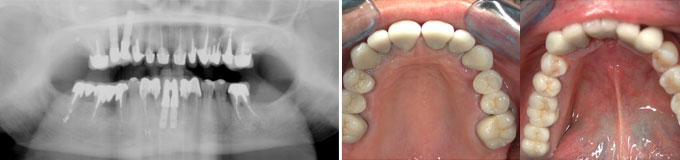

J’ai des caries partout, des dents manquantes, je veux l’idéal.

Toutes les dents manquantes sont remplacées et le sourire refait.

Une situation de pertes dentaires multiples et infections sous des racines naturelles.

Final : traitements de racines effectués et dents manquantes remplacées.